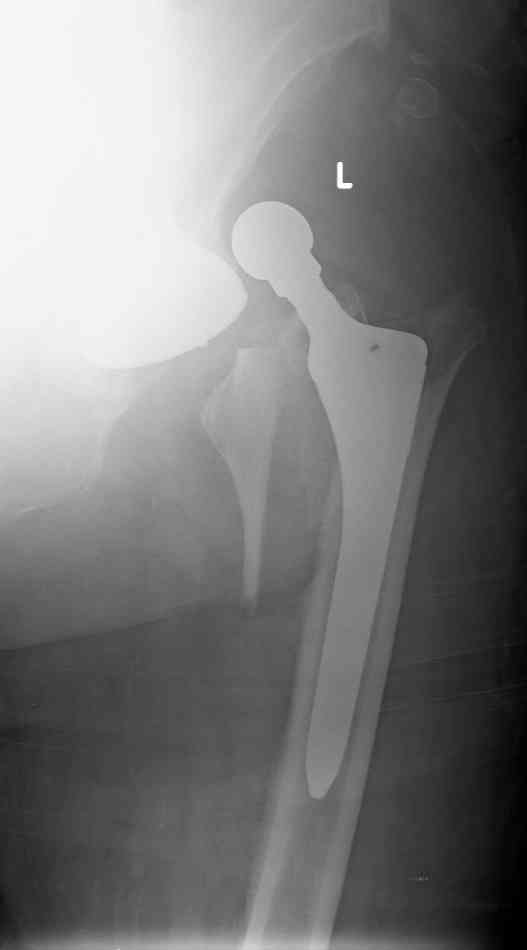

In the first I'd like to thank all collegues for fast and professional reaction to my case.Among I am also like to clarify, that joint was very stable at the end of surgery and another joint, which was operated few years ago has same offset of proximal femur.The patient was falled during confiuse state,so this is pure traumatic case.

Exactly ,I used Zimmer proximally coated stem.And

I am agree with Mr.Chris Wilson that Vancouver

classification isn't appropriate to this case.

Sure I will go to revision procedure with use distal fixation. I am going to use Corin long stem with distal locking.If during surgery be made clear that socket position isn't accetable I am ready to change component,increased head to 36mm and to use constrained liner.